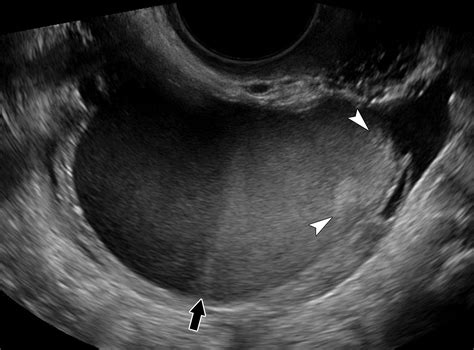

• Size and Shape: Normal ovaries are typically almond-shaped and measure about 2-4 cm in length, 1.5-3 cm in width, and 1-2 cm in thickness.

• Follicles: The presence and size of follicles are crucial indicators of ovarian function. During the menstrual cycle, follicles develop and release eggs.

• Cysts and Tumors: The absence of cysts or tumors is a positive sign, indicating normal ovarian health.

• Regular Ovarian Size: Ovaries that are within the normal size range and have a regular shape.

• Absence of Abnormalities: No signs of cysts, tumors, or other abnormalities.